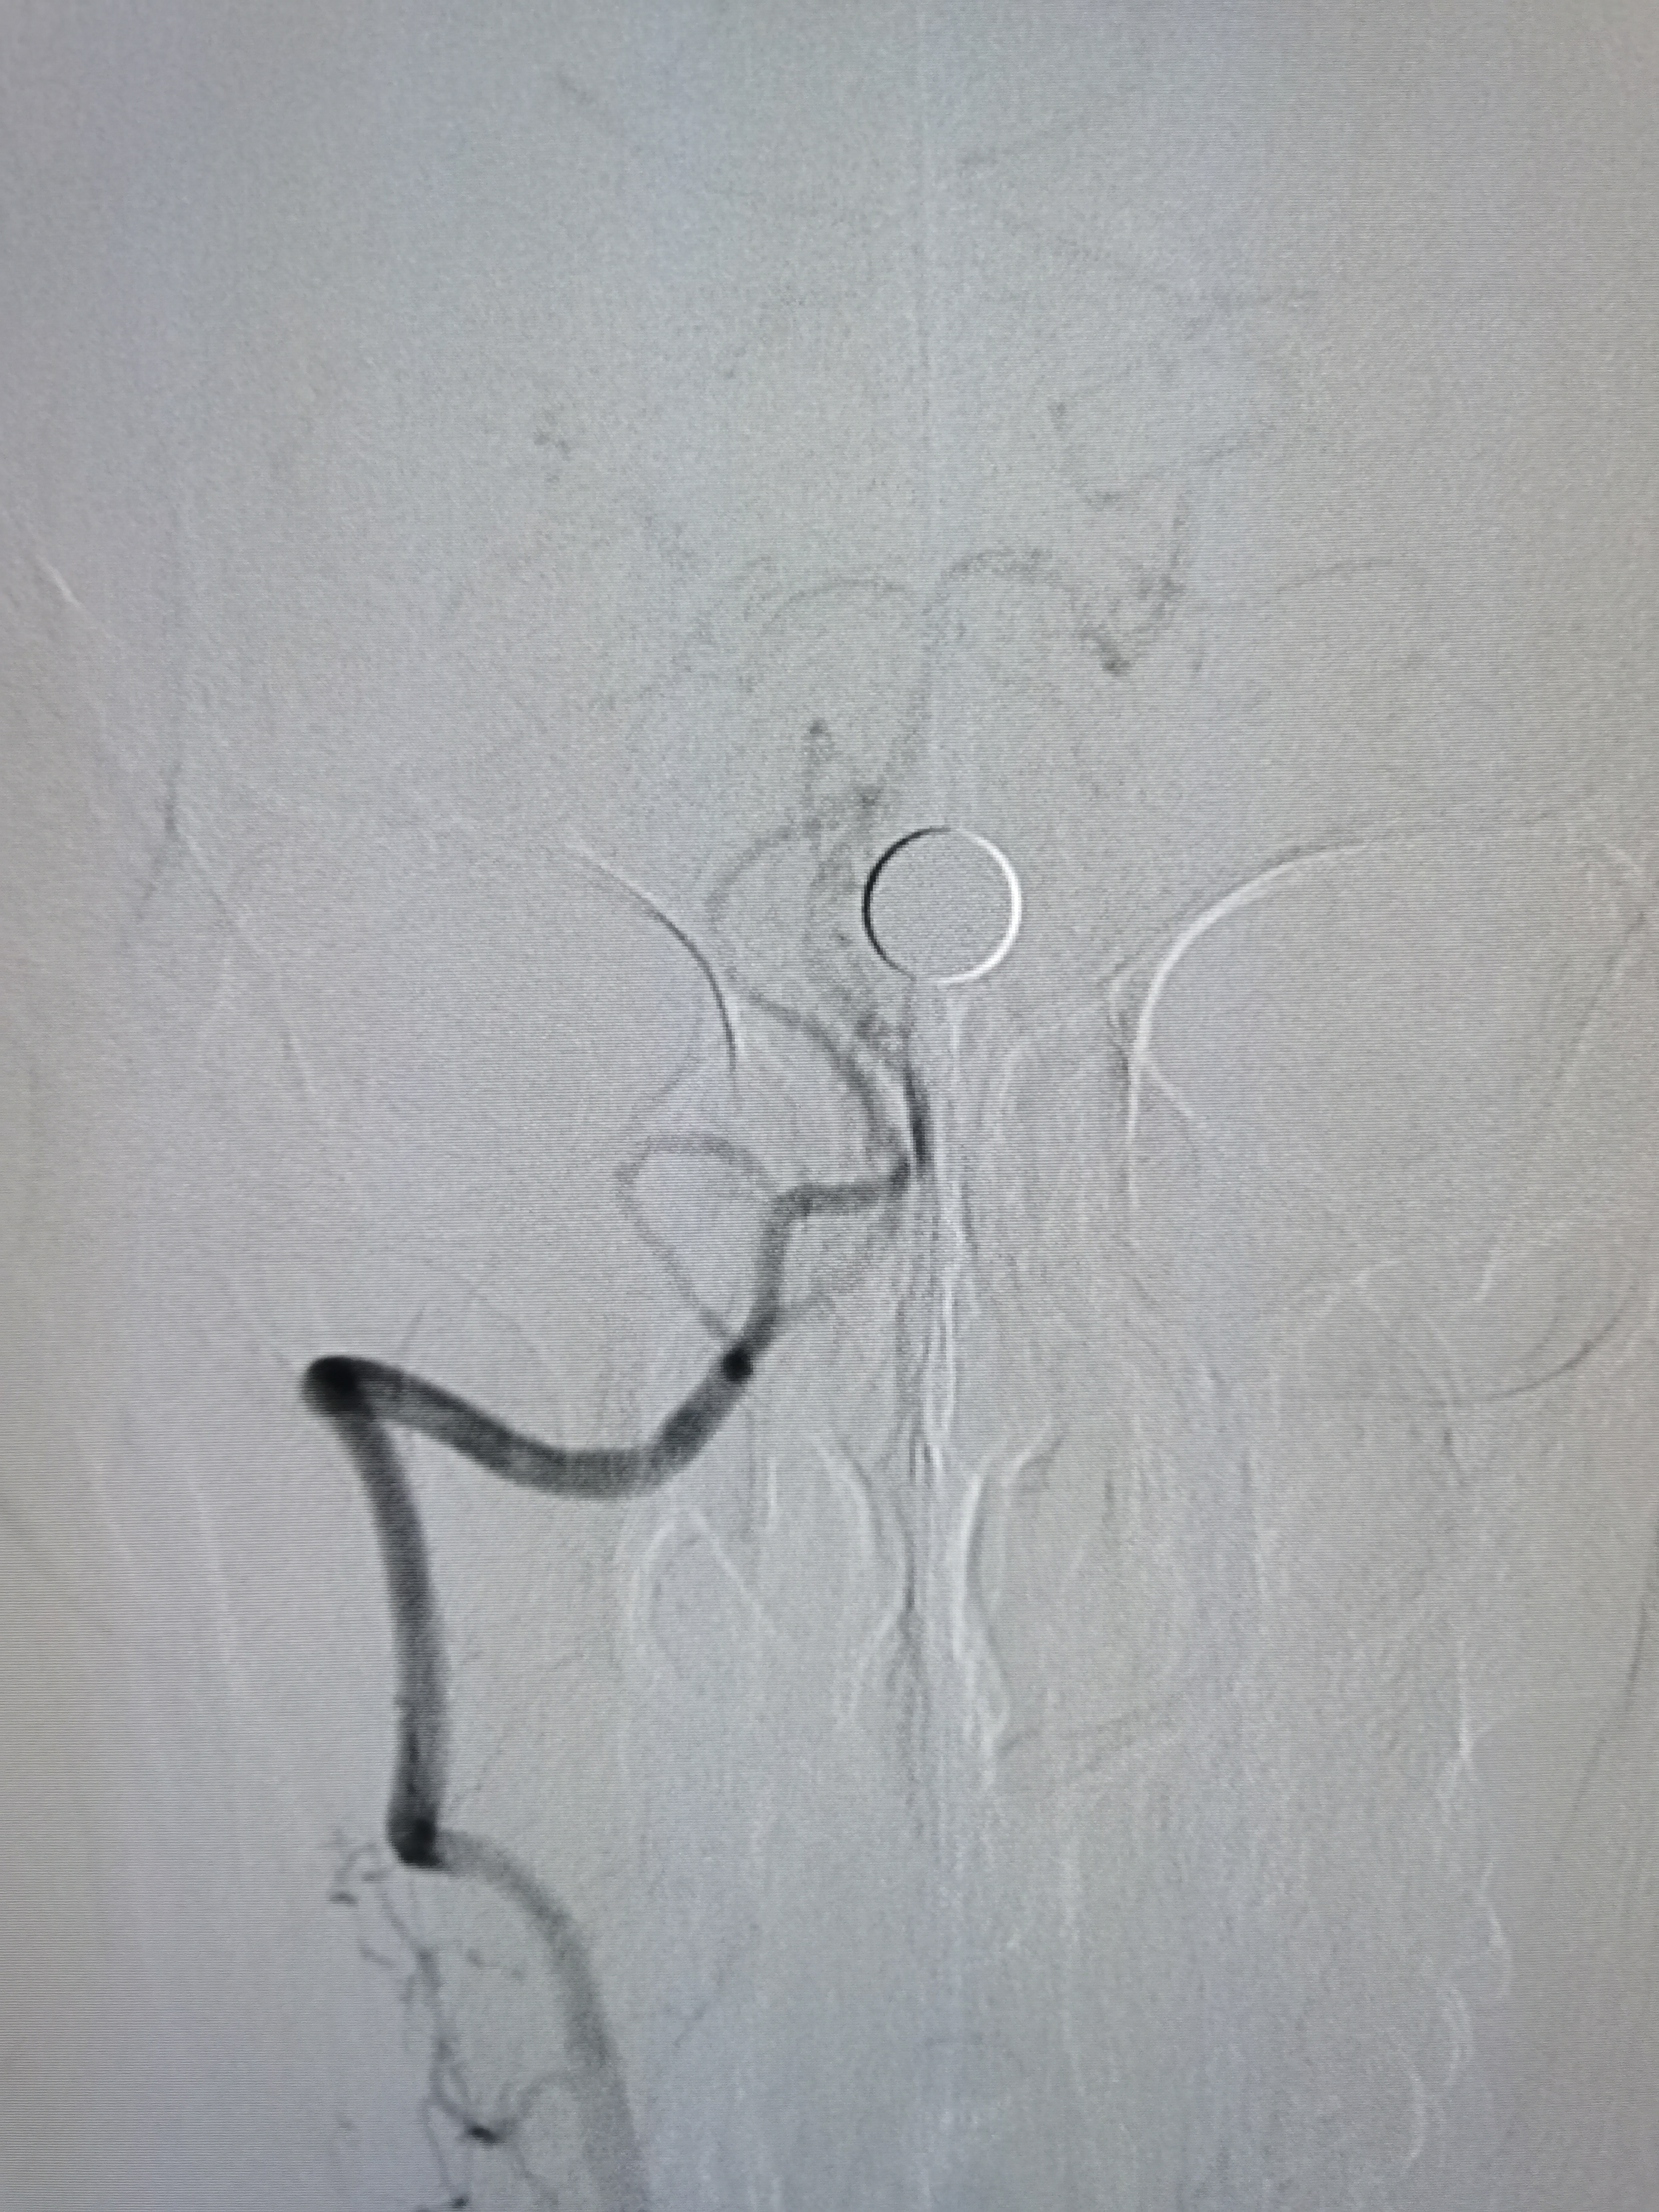

球扩后造影见狭窄解除,豆纹动脉显影良好,远端血供改善,未见夹层征象。

正位造影见狭窄解除,颅内血流通畅。

观察15分钟后造影未见明显弹性回缩。

侧位造影见颅内血流通畅。

球囊扩张后狭窄解除,决定不再植入支架,撤出导丝造影见血管通畅,遂逐级撤出各级导管,结束手术。